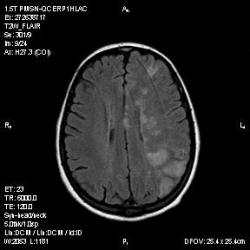

Из анамнеза - Женщина 45 лет. За год похудела на 15 кг (со слов матери), в последние месяцы случались эпизоды потери сознания. Онкозаболеваний и прочая в анамнезе нет. Сознание спутанное, из особенностей в анализах только подъем амилазы крови.

К сожалению, не владею методом КТ, но учитывая наличие неравномерного уплотнения в мозговых структурах с элементами очаговых "вкраплений", единственное, что приходит на ум - это рассеяный склероз. Хотелось бы уточнить, что беспокоило пациентку в течение последнего года кроме потери веса и эпизодов потери сознания? Была ли какая-либо очаговая неврологическая симптоматика? Отмечались ли какие-либо расстройства в двигательной или чувствительной сфере и т.д.? С уважением Helenmar.

И это точно не РС, т.к. характер очагов другой, ни один из них не копит контраст, нет субтенториальных очагов (извиняюсь, я этого в сообщении не указал), нет клиники.

"Раскрою" карты. Мы подумали о синдроме MELAS (mitochondrial encephalomyopathy, lactic acidosis and stroke) - дословно, митохондриальная энцефаломиелопатия, лактоацидоз и инсульт. В качестве дифференциальной диагностики можно было бы предположить вирусный энцефалит, но опять-таки, расположение очагов смущает - только с одной стороны и в абсолютно различных структурах.

В данном случае мы видим импульную последовательность FLAIR - режим с подавлением сигнала от воды, поэтому ликвор гипоинтенсивен, а также (вторая серия) - изображения, взвешенные по T1 после введения контрастного препарата. На T1 жидкость (ликвор) также представляется гипоинтенсивной. Зато на этих сериях гиперинтенсивны сосуды, т.к. контрастное вещество циркулирует в кровяном русле.

Изменения носят сосудистый характер. Процесс достаточно острый, имеется объемное воздействие, борозды левой гемисферы компремированы. По поводу MELAS синдрома очень сомневаюсь, почему поражена только левая гемисфера? Надо делать МР-ангиографию, смотреть нет ли стеноза

MELAS синдром - дебютирует с детских лет, характерен целый комплекс неврологических проявлений, заболевание генетическое, поражение системное, хотя есть множество вариантов митохондриального поражения, все же сомнительно. Хотелось бы акцентировать внимание, что гиперинтенсивные очаги есть в мозолистом теле, поражены выражено перивентрикулярные отделы, U -пути, белое вещество, поэтому так категорично демиелинизацию не вычеркивала бы из дифряда ( хотя тоже нетипично односторонее поражение). Думаю, для объективных выводов все же мало общей информации о пациентке, были ли клинические эпизоды раньше, чем объяснить такую потерю веса (возможно есть проявление паранеопластического синдрома?). Ну и МРТ-контроль в динамике, ангиография.

Да, неоднозначный случай. Точно не РС и не ОНМК. Я бы написала асимметричную лейкоэнцефалопатию неясного генеза. Можно было бы думать о лимфоме (полифокальное поражение, да еще мозолистое тело вроде бы задействовано (эх, сагиттальчики бы)). Но! Учитывая отсутствие накопления КВ.... Ну и надо исключать интоксикацию, всяческие аутоиммунные процессы (в т.ч. и васкулиты), сахарный диабет, ну и естественно наследственную патологию обменных процессов. УУУх! Вот.......

Имхо ишемический онмк в бассейне сма. Особенно показательны 5-й и 6-й файлы, отграничение как раз на границе бассейнов средней и перикаллёзной. Плюс одностороннее поражение.